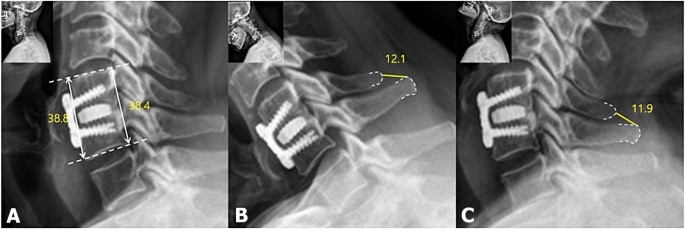

Dynamic lateral radiographs were used to assess ISM in a 150% magnified view between the most prominent point of the spinous process in the fusion segment. More than 1 mm change of ISM between 6 weeks and 12 months simultaneously post-operatively was regarded as pseudoarthrosis22. In the lateral radiograph, cage subsidence was defined as > 3 mm loss at the one-level segment heights, which were calculated as the mean anterior and posterior vertebral body heights between the upper and lower margins of the upper and lower vertebral bodies, respectively, at the fused segment between immediate post-operative and post-operative 12 months (Fig. 2)23. A CT scan was used to evaluate the fusion status, which is defined as bone bridging formation around graft material in the fusion segment 12 months post-operatively (Fig. 3). Fusion status was assessed based on the agreement of two orthopedic surgeons with 5 and 8 years of experience who were not involved in the treatment. Inter- and intra-observer agreements were assessed using Cohen’s kappa value (95% confidence interval) according to Landis et al.’s method24. Two reviewers analyzed the CT scans and dynamic radiographs for bone bridging formation around the cage and ISM after a 3-week interval to investigate the intra-rater agreement. Disagreements in the radiographic results for assessment of fusion status were resolved through discussion between reviewers with a unanimous decision. All radiographic parameters were measured using an internal caliper tool in the software (Centricity 3.0, General Electric Medical System, Milwaukee, WI, USA).

12 months postoperative dynamic lateral radiograph of a 66 years-old woman. Length of anterior and posterior border of fusion segment was measured (A). If there is 3 mm or more shorten is calculated in difference with mean of anterior or posterior border between preoperative and postoperative 12 months, defined as subsidence. Inter-spinous motion (ISM) is measured between most prominent point of spinous process within fusion segment in (B) Flexion and (C) Extension view. if there is > 1 mm difference, was defined as pseudoarthrosis.